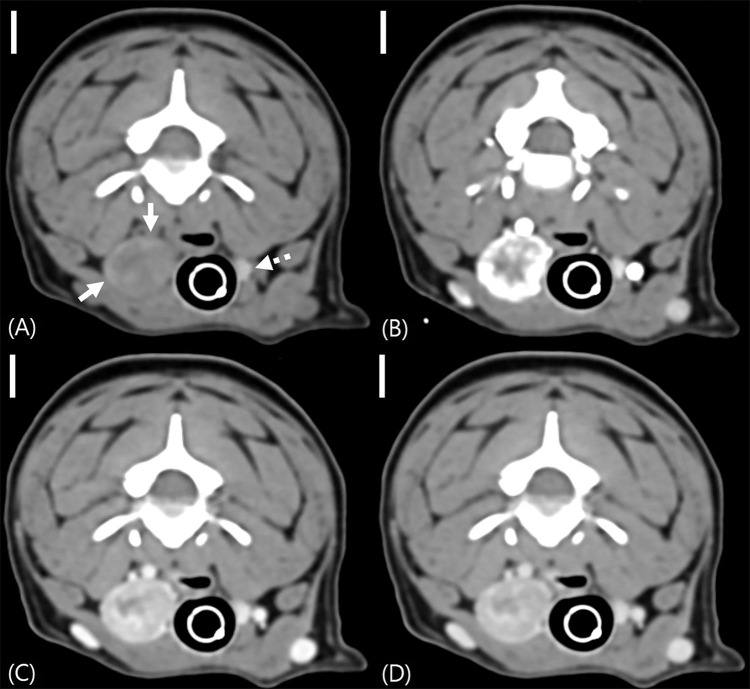

An 11-year-old Bichon Frise presented with a right cervical mass. Computed tomography revealed a thyroid mass without significant lymphadenopathy; however, the caudal portion of the ipsilateral retropharyngeal lymph node exhibited marked hyperattenuation on pre-contrast images. Histopathology of this lymph node confirmed the presence of metastasis from thyroid adenocarcinoma. The caudal portion of the lymph node displayed dense tumor cells with abundant sodium/iodide symporter-positive cells. The observed hyperattenuation of the lymph node was presumed to result from iodide deposition associated with the metastasis of the thyroid tumor. This case suggests that even in the absence of lymph node enlargement, hyperattenuating lymph nodes should raise suspicion for metastasis in dogs with thyroid tumors. However, as this is a single case, further studies are needed to determine the broader applicability of this finding.

Abstract Image